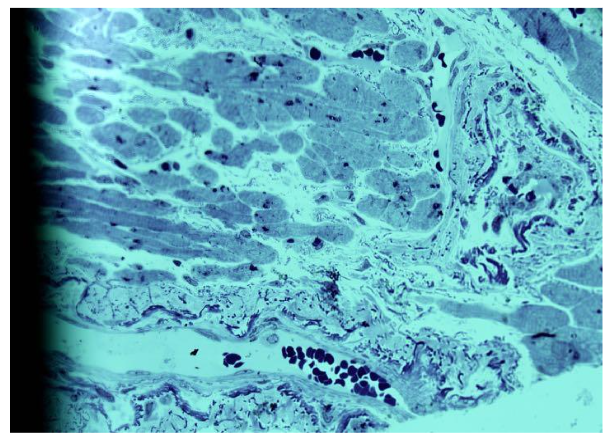

The obtained images of arterioles were characteristic for each individual patient, showing both similarities and differences. The arterioles displayed variable lumen diameters, ranging from very large to small profiles. Wall thickness also varied, with some arterioles showing pronounced intussusceptive invaginations into the lumen. In certain cases, bridges connecting opposite arteriolar walls were observed, sometimes multiple in a single vessel.

Atherosclerotic changes were particularly notable in larger arterioles. These vessels exhibited elongated lumens, significant wall thickening, and abundant smooth muscle cells. Some large arterioles showed up to two convolutions at different ends of the lumen. Evidence of newly forming arterioles was observed, including residual fragments indicating separation. Notably, the newly separated arterioles differed markedly in lumen size compared to the parent vessel. In some separated segments, chambers were present, indicating the formation of a new convoluted vessel.

Frequently, arterioles with thickened walls consisted of multiple aligned lumens of different sizes, suggesting formation through bridging of opposite walls.